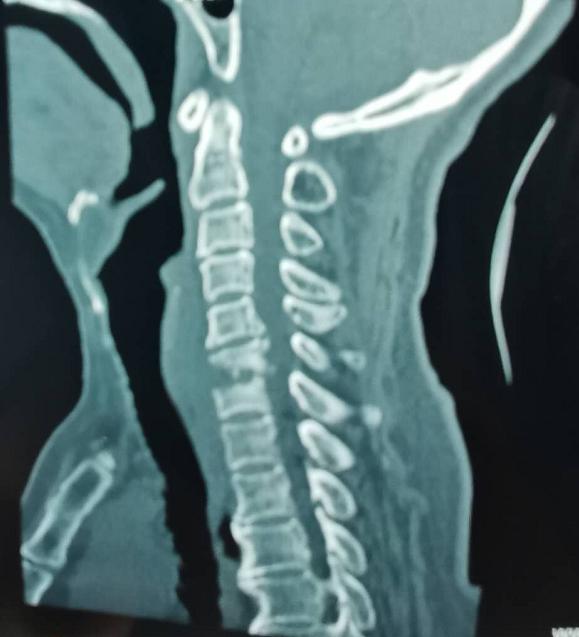

王先生今年64岁,入院时乳头以下全身麻木、不能走路、二便障碍,经核磁及CT检查发现“颈6椎体占位性病变”,且从发病至不能走路只经历约1个月时间,如不能得到及时治疗,患者出现高位截瘫的风险非常高。经市二院骨科医院骨八科主任田晓东(院长助理)及其团队的精心治疗,为患者进行颈胸段前后路联合手术、病灶清除内固定手术,术后一周,王先生感觉麻木消失,能自行下床活动,目前王先生恢复良好。

术前影像